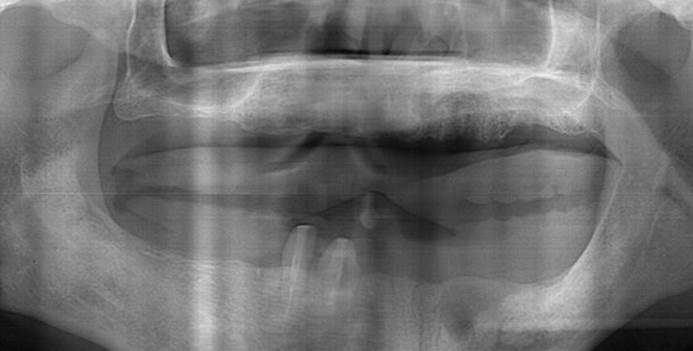

Clinical case: AFull transition from natural teeth to all-on-6 bridges

with AnyRidge implants

- Courtesy of Dr. Rabih Abi Nader, UAE -